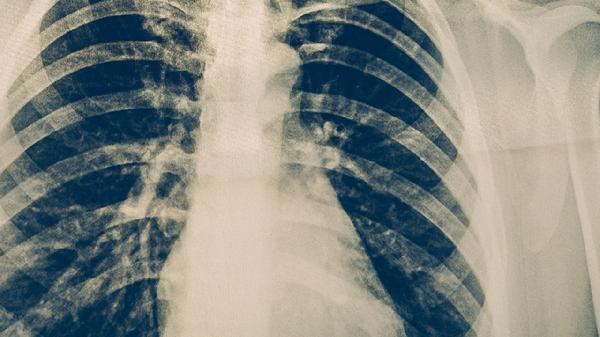

肺癌靶向药物治疗是通过特定药物精准抑制肿瘤生长信号通路的治疗方法,主要适用于表皮生长因子受体突变、间变性淋巴瘤激酶重排等驱动基因阳性的非小细胞肺癌患者。靶向药物主要有吉非替尼片、厄洛替尼片、克唑替尼胶囊、阿来替尼胶囊、奥希替尼片等,需严格遵循基因检测结果选择用药方案。

接受靶向治疗期间应保持均衡饮食,适量增加优质蛋白和维生素摄入,避免葡萄柚等影响药物代谢的食物。每周进行150分钟中等强度运动有助于改善治疗耐受性,但需避免剧烈运动导致疲劳。定期复查胸部CT和肿瘤标志物,出现持续咳嗽加重或不明原因体重下降需及时复诊。严格遵医嘱调整用药方案,不可自行增减剂量或中断治疗。